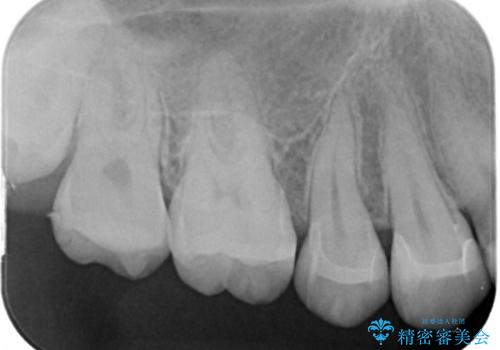

- 歯の健診にて来院。

レントゲンを撮った時にう蝕があったため、拡大鏡下でう蝕が残っていないか確認し

セラミックの詰め物(e-maxインレー)にて治療を行いました。

う蝕が大きくなると、歯の神経にまで広がり痛みが出ます。

痛みが出る前に治療をしておくことで歯に対しての予後が良いです。